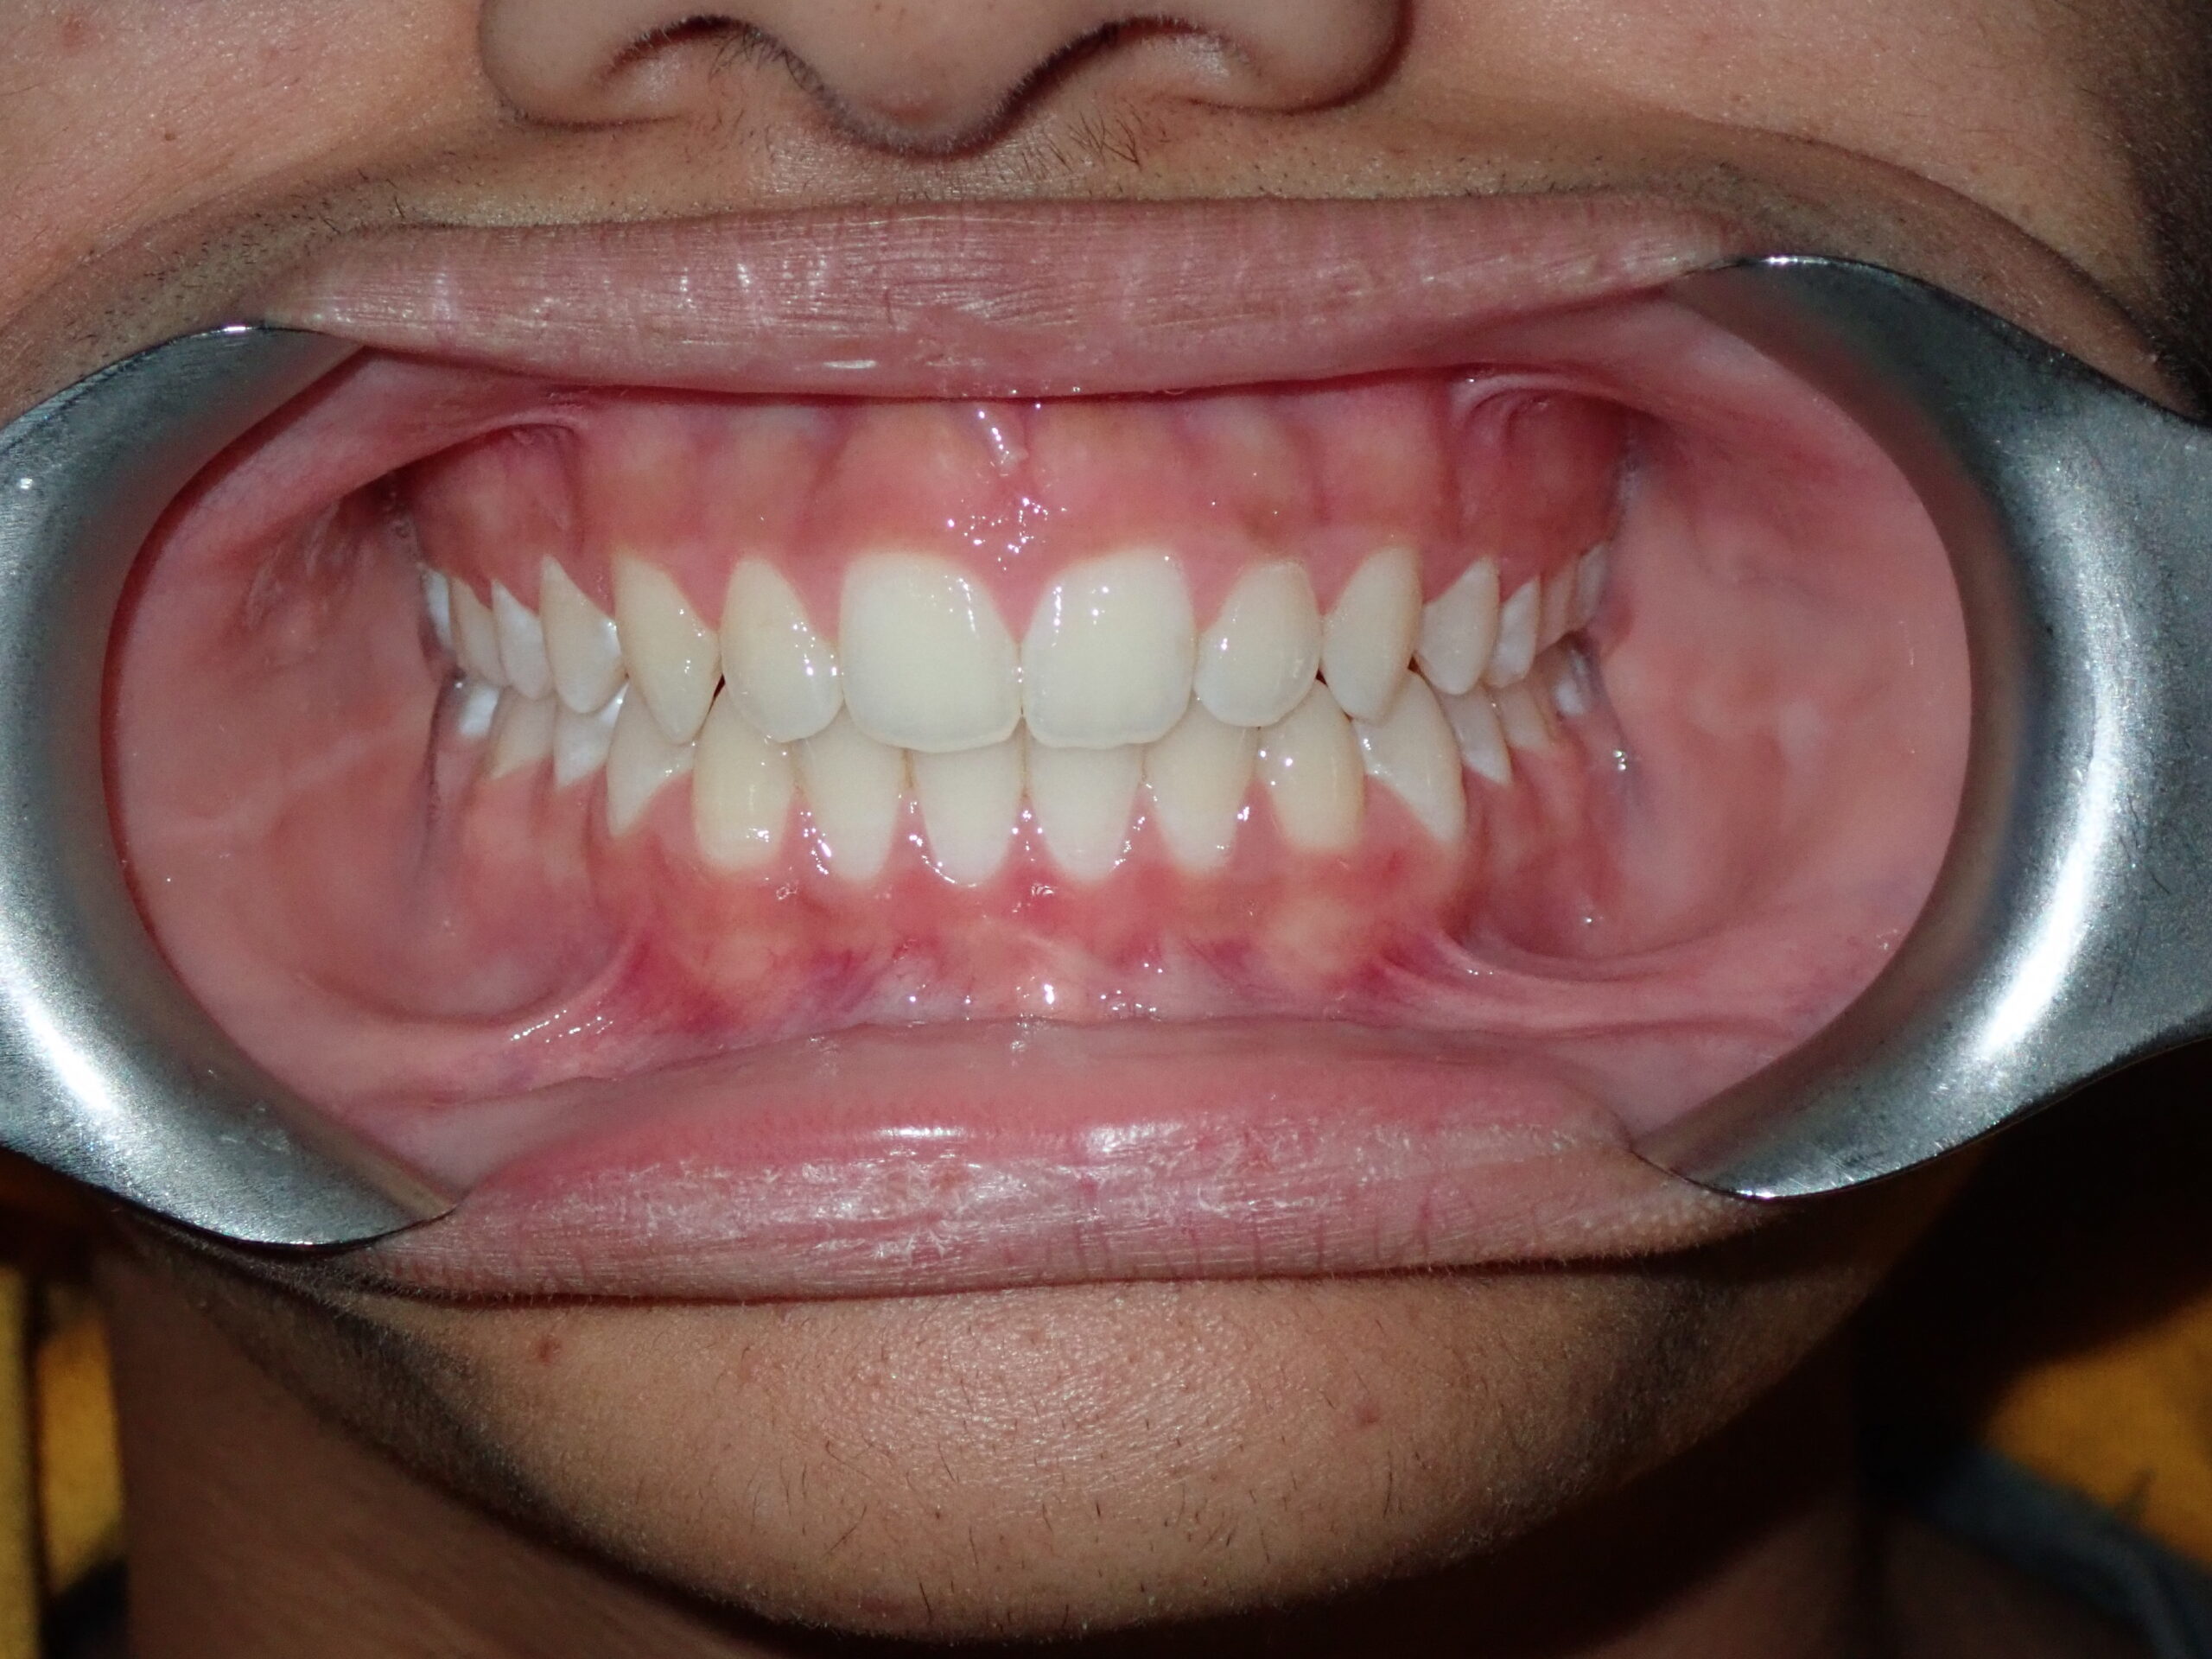

Patient Resultsنتائج المرضى

Real Results. Real Patients.نتائج حقيقية. مرضى حقيقيون.

Philosophy of Careفلسفة الرعاية

"Our mission goes far beyond merely straightening teeth. We structurally optimise the jaws and facial profile to unlock a broader smile, alleviate joint pain, and restore healthy, natural breathing — delivering life-changing results without surgery whenever possible." "مهمتنا تتجاوز بكثير مجرد تقويم الأسنان. نُحسّن بنيوياً الفكين والملامح الوجهية لإطلاق ابتسامة أوسع وتخفيف ألم المفاصل واستعادة التنفس الصحي الطبيعي — نتائج تغيّر الحياة بدون جراحة كلما أمكن."